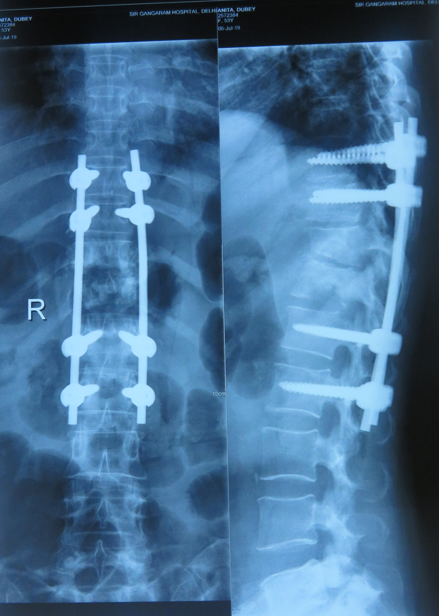

Surgical Intervention

Surgery becomes necessary when there's nerve compression, spinal instability, large abscess, or when infection doesn't respond to medication.

- Restores spinal stability and function

- Pressure on nerves or spinal cord

- Spinal instability due to bone destruction

- Large abscess formation

- Infection not responding to medication